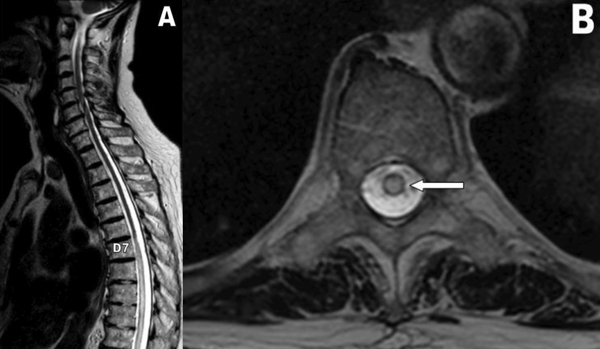

Paciente masculino de 75 años de edad, con antecedente de insuficiencia renal y canal estrecho lumbar, presentado clínicamente como lumbociatalgia bilateral con claudicación de la marcha a menos de 100 mts. Se realizó cirugía descompresiva con artrodesis L4-L5 a principios del 2021 en otra institución. El procedimiento se realizó sin complicaciones inmediatas y posterior alta institucional a los 5 días posquirúrgicos. A los 12 meses, el paciente nuevamente presentó cuadro progresivo de dolor lumbar similar al anterior, con predominio del componente ciático, más alteración de la marcha. Ante tal evolución, se decidió realizar una Resonancia Magnética Nuclear (RMN) dorsolumbar, donde se observó una hiperintensidad medular central en secuencia T2, que se extendía desde los últimos segmentos dorsales a los primeros lumbares (Figura 1). El cuadro se interpretó en ese momento como siringomielia, con exploración de la zona comprometida sin hallazgos relevantes y con muestra de anatomía patológica con posterior informe de edema medular.

Figura 1: RMN columna dorsal en secuencia T2 corte sagital y axial (A-B), revela hiperintensidad central (flecha)